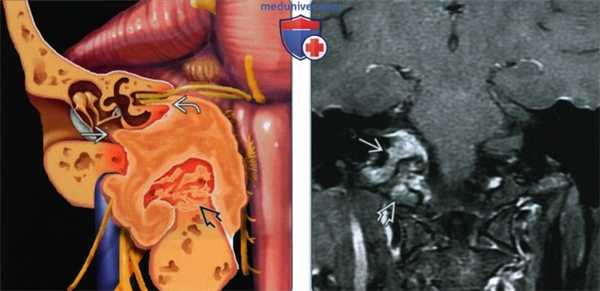

(Слева) На рисунке коронального среза показана крупная менингиома яремного отверстия, прорастающая в среднее ухо, костный мозг основания черепа и внутренний слуховой проход. Обратите внимание, в яремном отверстии опухоль окружает черепные нервы (IX-XI пары).

(Справа) При МРТ Т1 ВИ FS с КУ в корональной проекции определяется крупная менингиома яремного отверстия, прорастающая в костный мозг основания черепа. Для менингиом яремного отверстия характерен центрифугальный вектор распространения, часто они разрастаются вдоль поверхности твердой мозговой оболочки и сквозь окружающие кости.